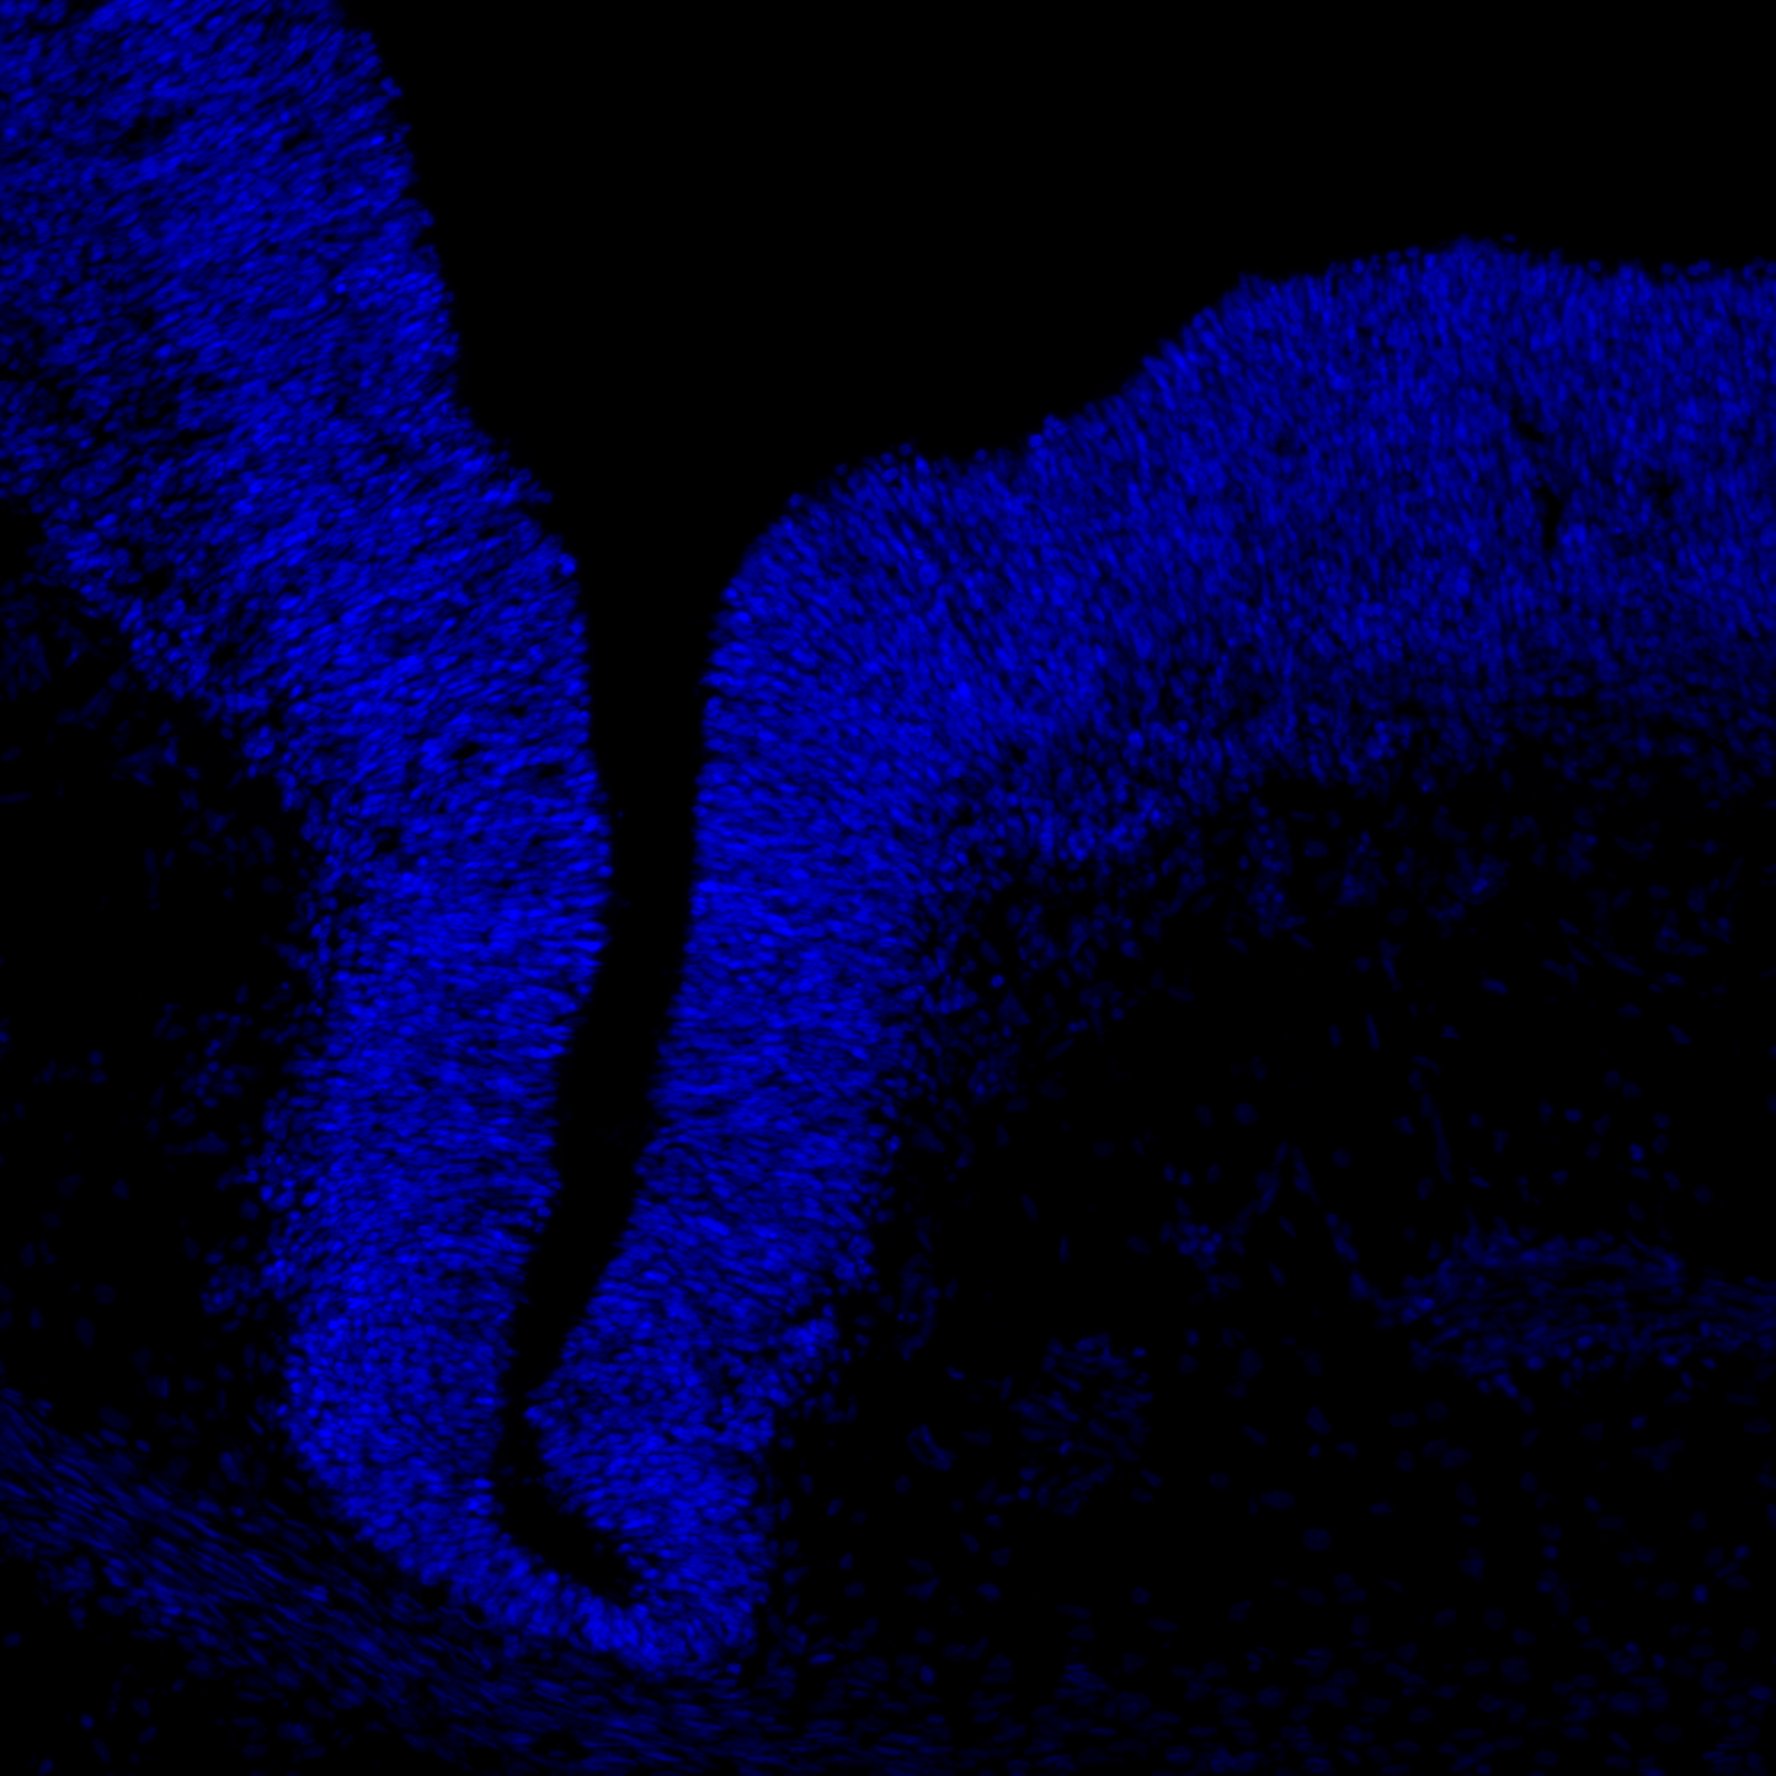

6PCW

DAPI

6PCW human midbrain